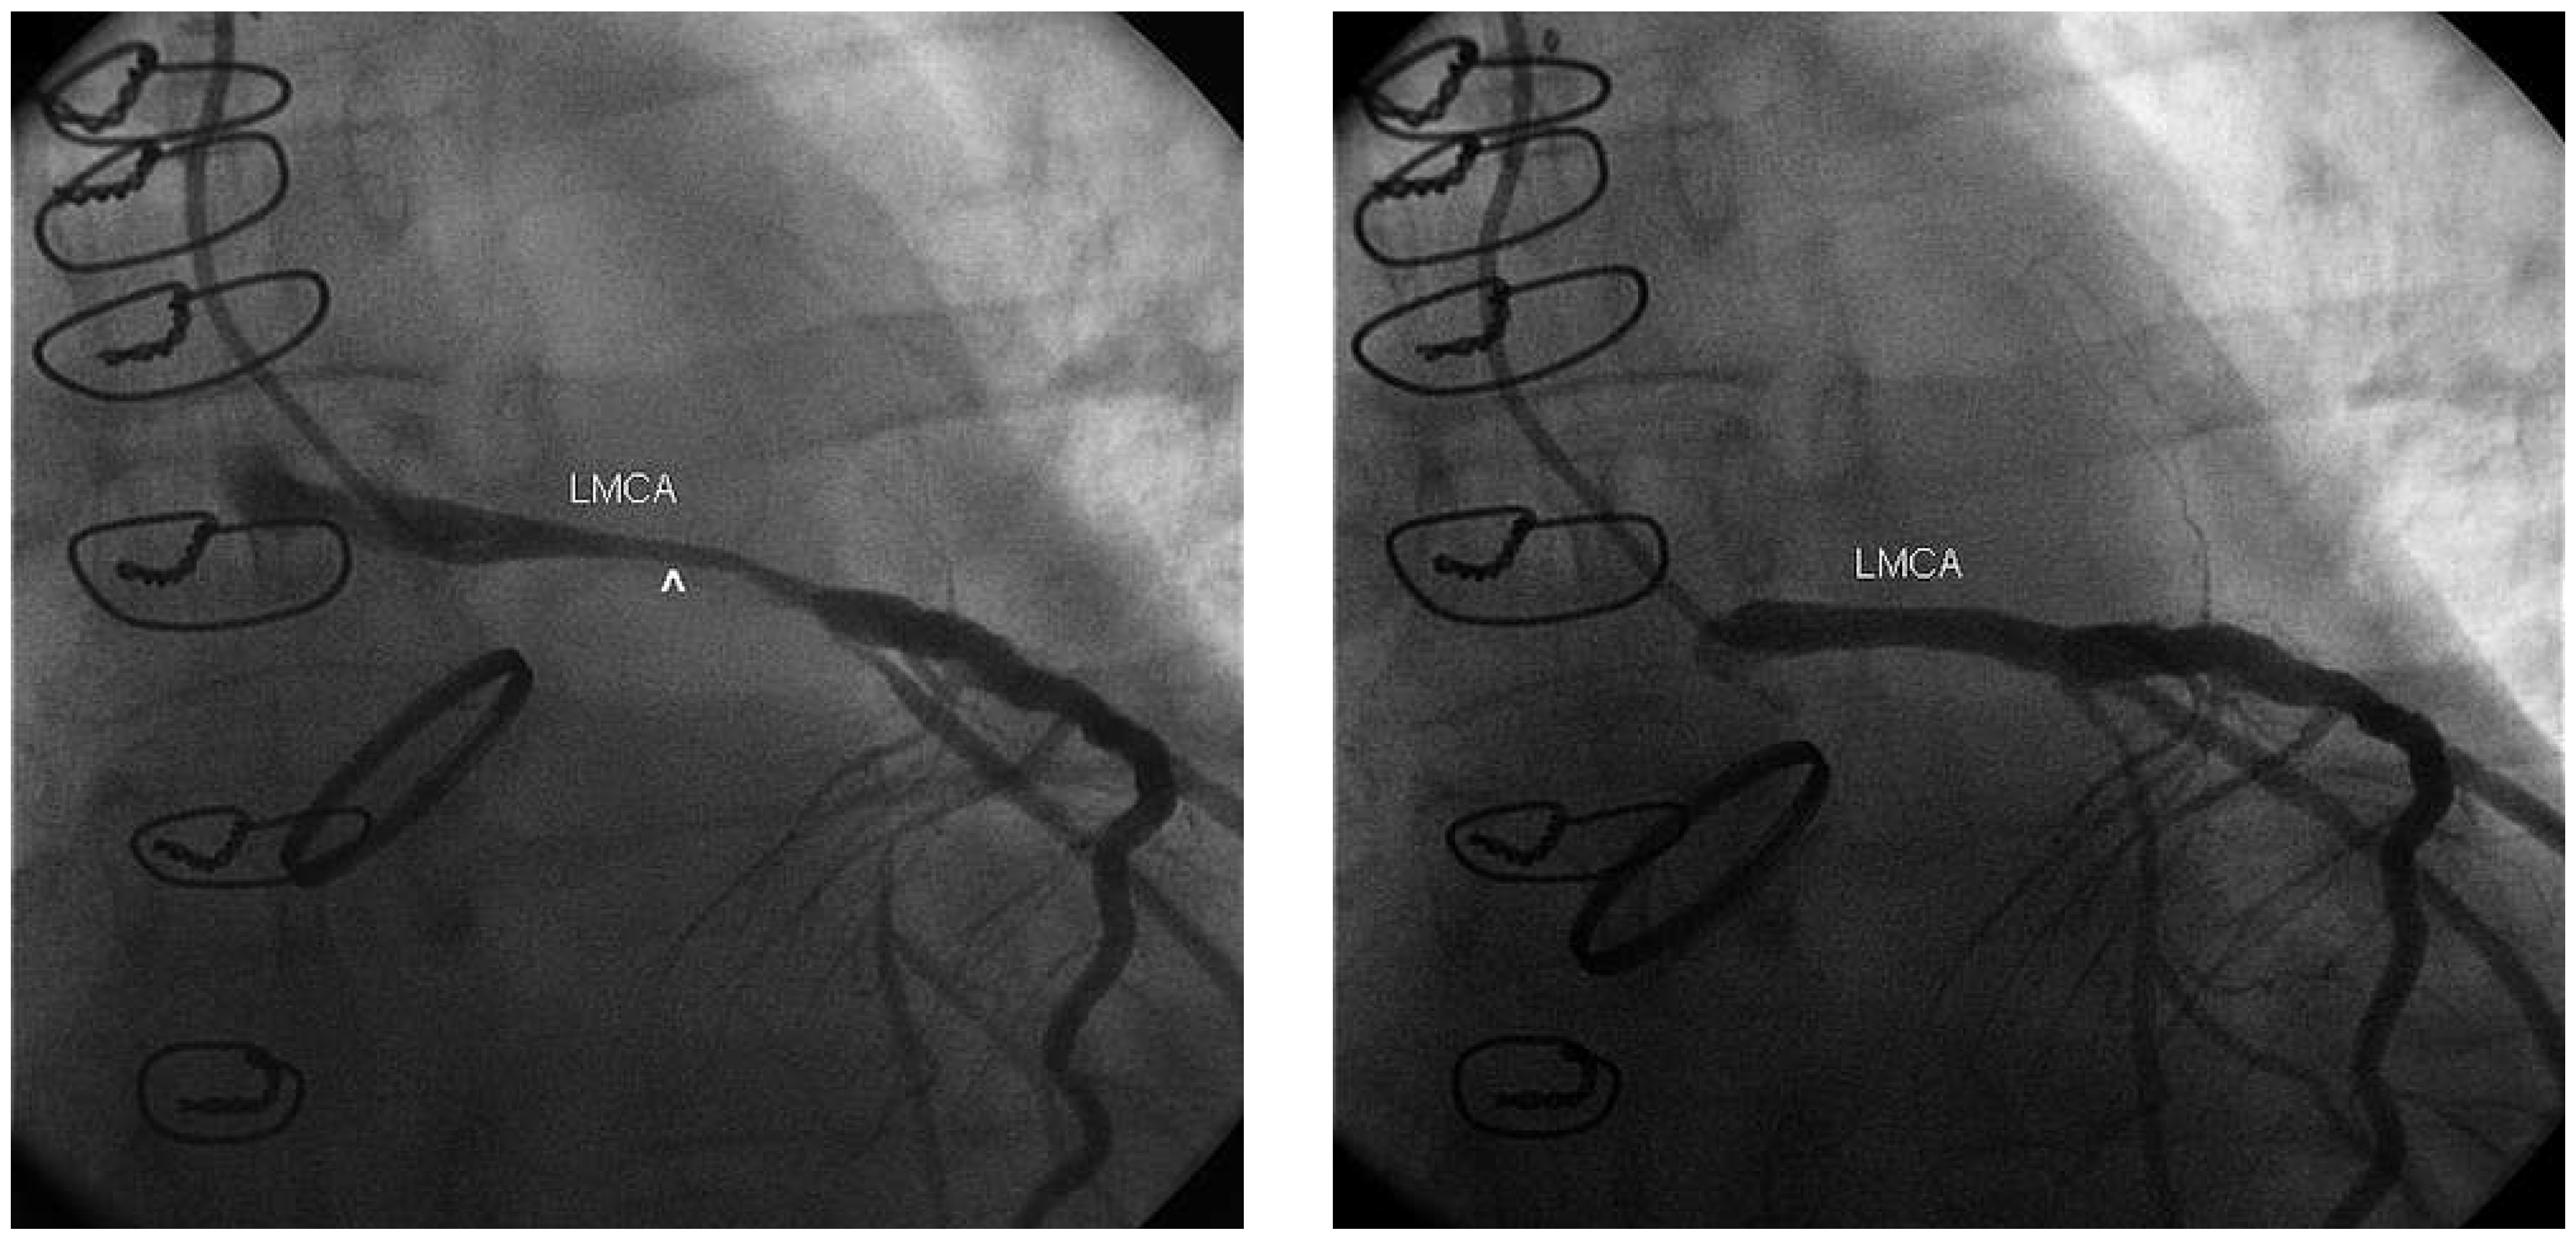

Partial Aortic Graft Disconnection Due to Endocarditis: A Rare Cause of Dynamic Coronary Artery Compression